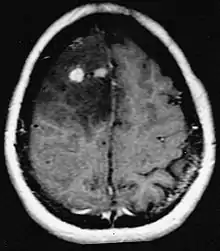

Metástases cerebrais

As metástases cerebrais são as neoplasias intracranianas mais comuns em adultos, sendo dez vezes mais comuns que os tumores cerebrais primários. Eles pisam em 20 até 40 por cento dos adultos com câncer e estão associados principalmente ao câncer de pulmão e mama e melanoma . Essas lesões resultam da disseminação de células cancerígenas pela corrente sanguínea e ocorrem mais comumente na junção da substância cinzenta e branca, onde a seção transversal dos vasos sanguíneos se altera, aprisionando embolias de células tumorais . 80 por cento das lesões ocorrem nos hemisférios cerebrais, 15 por cento no cerebelo e 5 por cento no tronco cerebral. Cerca de 80 por cento dos pacientes têm história de câncer sistêmico e 70 por cento têm múltiplas metástases cerebrais.

Avanços significativos foram feitos recentemente no diagnóstico e tratamento dessas lesões, resultando em melhora da sobrevida e controle dos sintomas. O início dos sinais e sintomas é semelhante ao de outras lesões maciças no cérebro. O método diagnóstico de escolha é a ressonância magnética com meio de contraste.